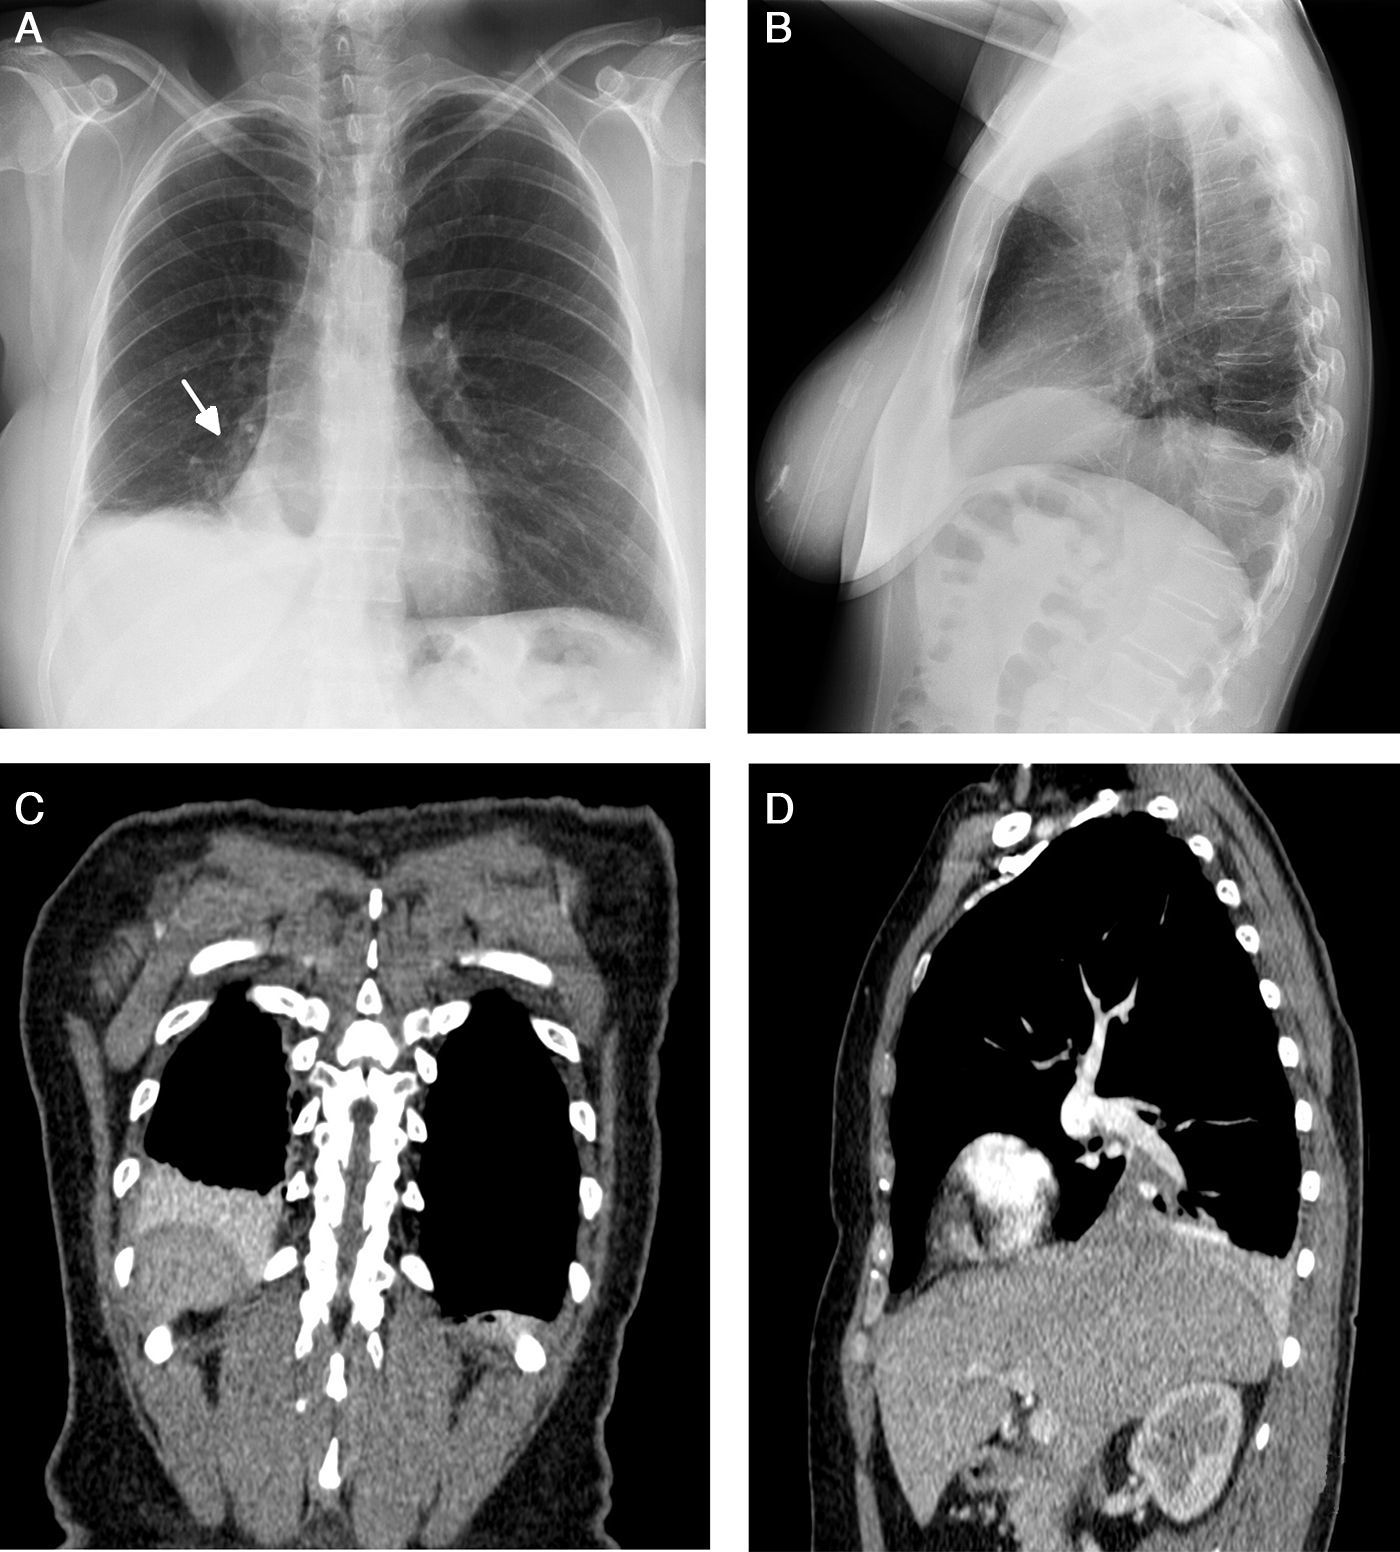

Atelectasis is an important indicator of potentially severe underlying disease that must be diagnosed as early as possible. One of the most common mechanisms is the reabsorption of air distal to respiratory tract obstruction. The chest X-ray is an excellent tool to diagnose atelectasis, and it is especially useful for ruling out central bronchial obstructions (e.g., from endobronchial tumors). If the signs of volume loss are not recognized correctly, the diagnosis and treatment can be delayed. This article describes the main findings of lobar atelectasis on chest X-rays and their correlations with CT findings, including the classic signs described in the literature and other, less known and sometimes subtle signs.